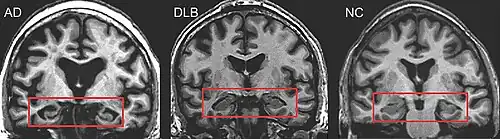

Medical imaging in AD and DLB

MRI of brain showing hippocampus atrophy (red rectangles), more prominent in AD than DLB, compared to normal control (NC)

PET or SPECT imaging can be used to detect reduced dopamine transporter uptake and distinguish AD from DLB.[56][144] Severe atrophy of the hippocampus is more typical of AD than DLB.[145] Before dementia develops (during the mild cognitive impairment phase), MRI scans show normal hippocampal volume. After dementia develops, MRI shows more atrophy among individuals with AD, and a slower reduction in volume over time among people with DLB than those with AD.[32] Compared to people with AD, FDG-PET brain scans in people with DLB often show a cingulate island sign.[32]